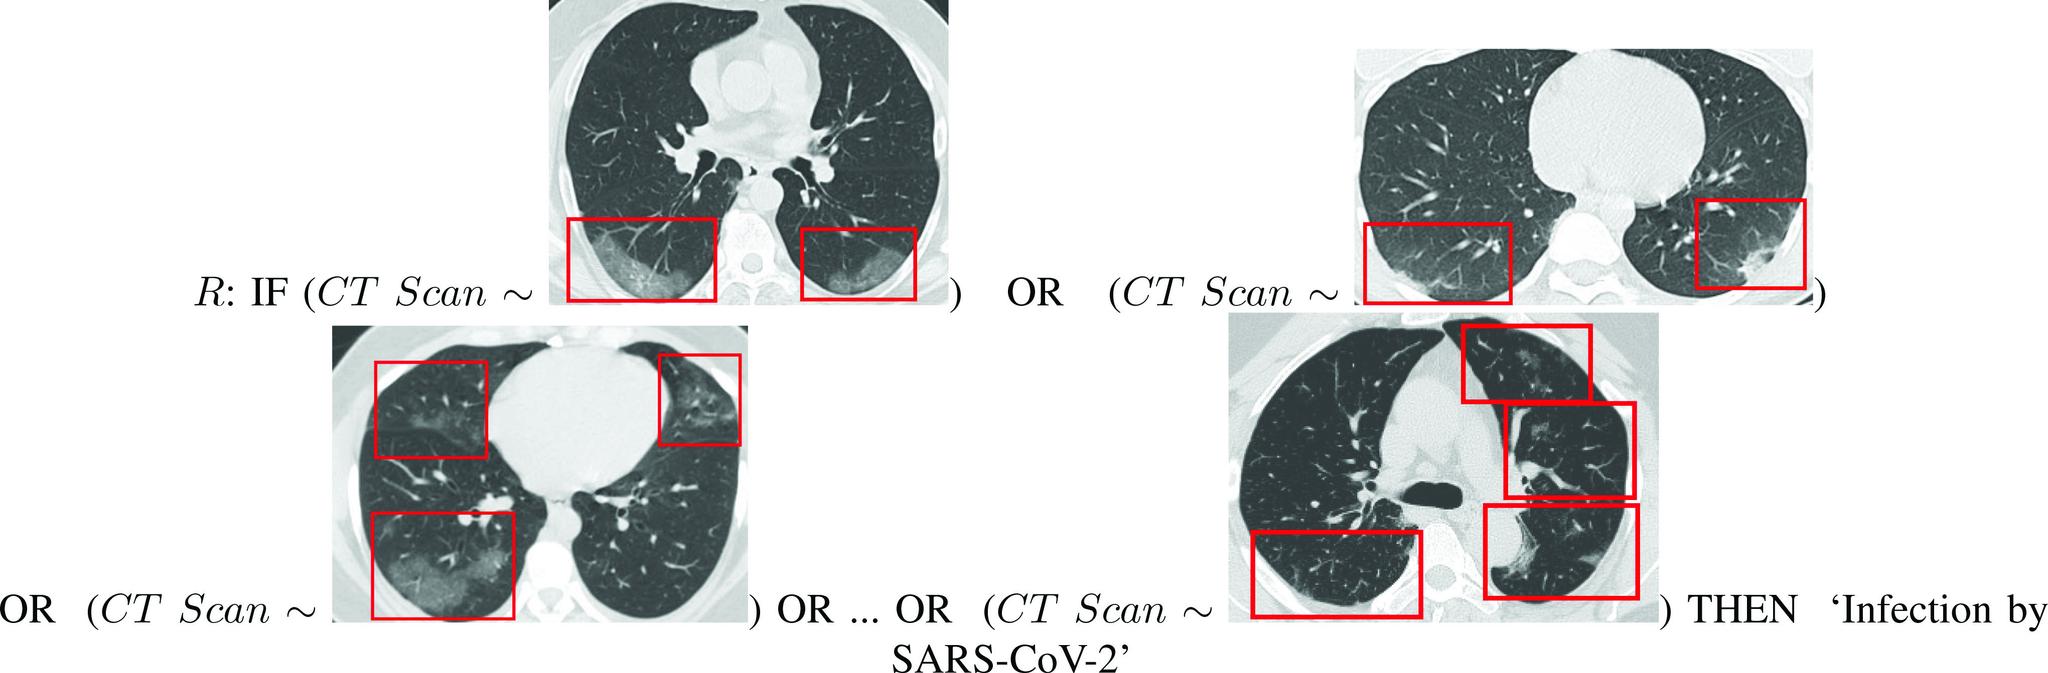

As COVID-19 hounds the world, the common cause of finding a swift solution to manage the pandemic has brought together researchers, institutions, governments, and society at large. The Internet of Things (IoT), artificial intelligence (AI)-including machine learning (ML) and Big Data analytics-as well as Robotics and Blockchain, are the four decisive areas of technological innovation that have been ingenuity harnessed to fight this pandemic and future ones. While these highly interrelated smart and connected health technologies cannot resolve the pandemic overnight and may not be the only answer to the crisis, they can provide greater insight into the disease and support frontline efforts to prevent and control the pandemic. This article provides a blend of discussions on the contribution of these digital technologies, propose several complementary and multidisciplinary techniques to combat COVID-19, offer opportunities for more holistic studies, and accelerate knowledge acquisition and scientific discoveries in pandemic research. First, four areas, where IoT can contribute are discussed, namely: 1) tracking and tracing; 2) remote patient monitoring (RPM) by wearable IoT (WIoT); 3) personal digital twins (PDTs); and 4) real-life use case: ICT/IoT solution in South Korea. Second, the role and novel applications of AI are explained, namely: 1) diagnosis and prognosis; 2) risk prediction; 3) vaccine and drug development; 4) research data set; 5) early warnings and alerts; 6) social control and fake news detection; and 7) communication and chatbot. Third, the main uses of robotics and drone technology are analyzed, including: 1) crowd surveillance; 2) public announcements; 3) screening and diagnosis; and 4) essential supply delivery. Finally, we discuss how distributed ledger technologies (DLTs), of which blockchain is a common example, can be combined with other technologies for tackling COVID-19.

随着新冠疫情席卷全球,迅速找到应对这一流行病的解决方案这一共同目标,将研究人员、机构、政府以及整个社会凝聚在了一起。物联网(IoT)、人工智能(AI)——包括机器学习(ML)和大数据分析——以及机器人技术和区块链,是技术创新的四个关键领域,人们巧妙地利用这些技术来抗击这场疫情以及未来的疫情。虽然这些高度相关的智能互联健康技术无法在一夜之间解决疫情,也可能不是应对危机的唯一答案,但它们可以提供对该疾病更深入的了解,并支持一线的疫情防控工作。本文综合讨论了这些数字技术的贡献,提出了几种应对新冠疫情的互补性多学科技术,提供了进行更全面研究的机会,并加速了疫情研究中的知识获取和科学发现。首先,讨论了物联网可以发挥作用的四个领域,即:1)追踪与溯源;2)通过可穿戴物联网(WIoT)进行远程患者监测(RPM);3)个人数字孪生(PDT);4)实际用例:韩国的信息通信技术/物联网解决方案。其次,解释了人工智能的作用和新应用,即:1)诊断与预后;2)风险预测;3)疫苗与药物研发;4)研究数据集;5)早期预警与警报;6)社会管控与假新闻检测;7)通信与聊天机器人。第三,分析了机器人技术和无人机技术的主要用途,包括:1)人群监测;2)公共公告;3)筛查与诊断;4)基本物资配送。最后,我们讨论了分布式账本技术(DLT),区块链就是其常见示例之一,如何与其他技术相结合来应对新冠疫情。